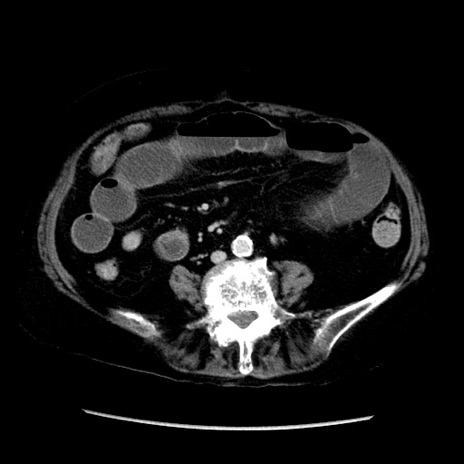

冠状断像